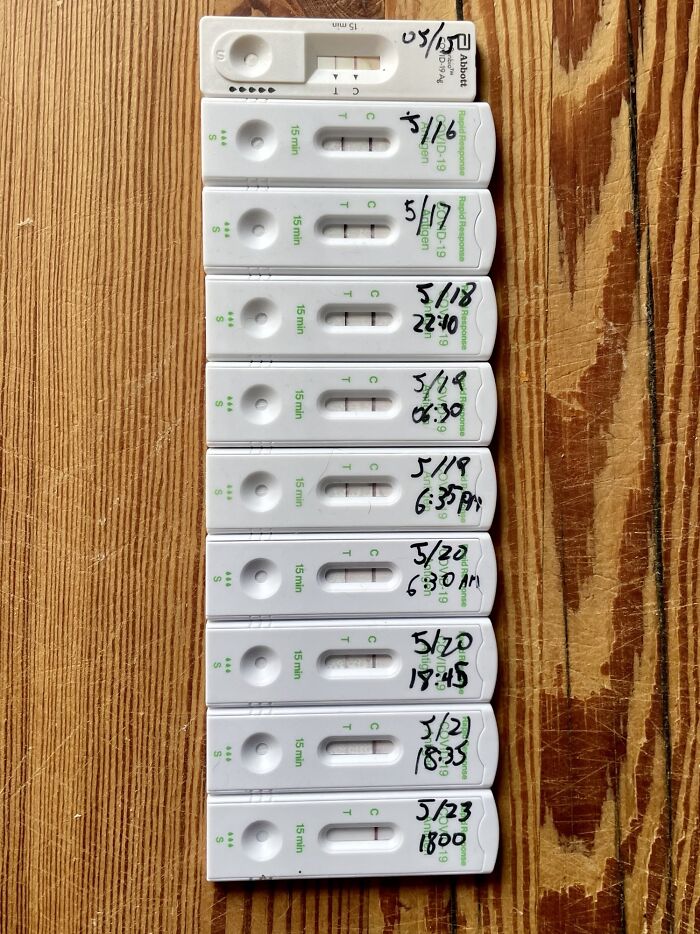

#120 My Covid Recovery

Image credits: Daeveed